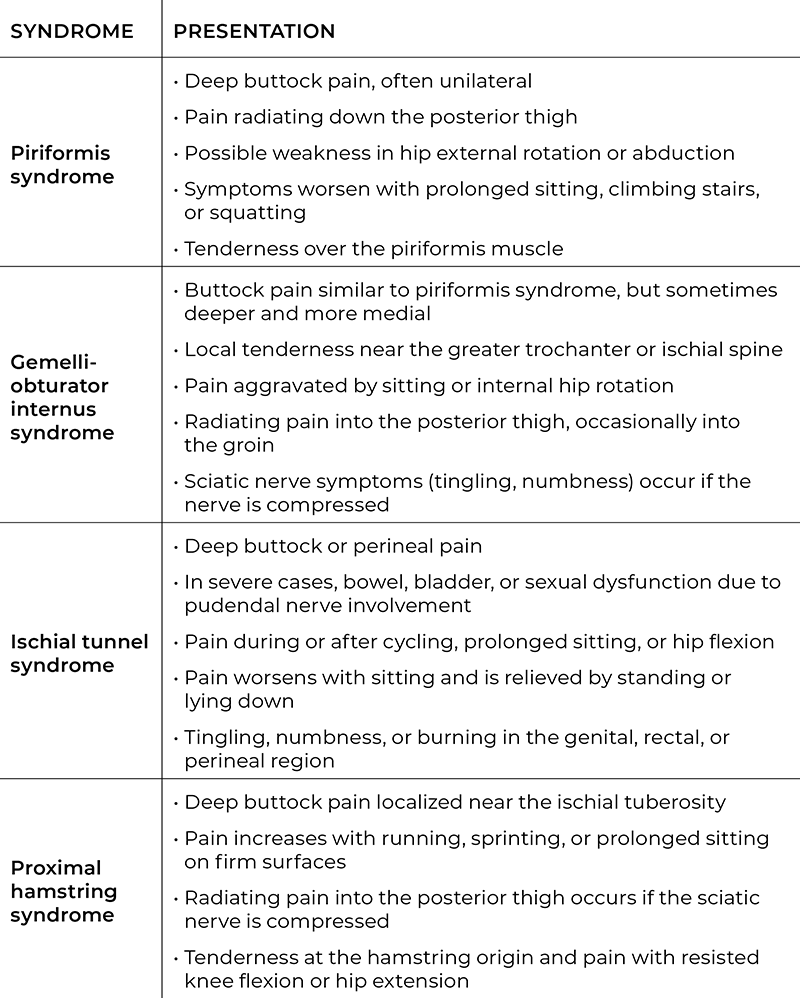

Each of these syndromes has distinct anatomical features but causes overlapping symptoms (see “Under the Deep Gluteal Syndrome Umbrella” table above). This overlap makes accurate assessment difficult without the use of imaging or extensive orthopedic testing.

Unlike lumbar radiculopathy (where nerve irritation originates in the spine), DGS involves entrapment at the level of the hip and pelvis, most often beneath or between the muscles of the deep six lateral rotators. While sciatic nerve entrapments are the most common, the definition extends to entrapments of the pudendal, superior and inferior gluteal nerves, obturator, and posterior femoral cutaneous nerves. Massage therapists are most familiar with the following syndromes:

Gemelli-obturator internus syndrome involves compression of the sciatic nerve by the tendon of the obturator internus and the adjacent superior and inferior gemelli muscles as the nerve exits the pelvis.

Ischial tunnel syndrome refers to entrapment of the pudendal nerve as it travels near the ischial spine or between the sacrospinous and sacrotuberous ligaments. Compression of the pudendal nerve can cause pain, tingling, or numbness in the perineum.

Piriformis syndrome occurs when the piriformis muscle compresses the sciatic nerve as it passes beneath or through the muscle in the greater sciatic notch. This entrapment is the most well-known presentation of deep gluteal syndrome.

Proximal hamstring syndrome involves compression of the sciatic nerve against the ischial tuberosity by hypertrophy, fibrosis, or scarring of the proximal hamstring tendons. It is a primary suspect when symptoms arise in athletes with chronic hamstring overload or injury.

Other syndromes that fall under the DGS umbrella are superior and inferior gluteal nerve entrapments, obturator nerve entrapment, posterior femoral cutaneous nerve entrapment, and quadratus femoris syndrome.